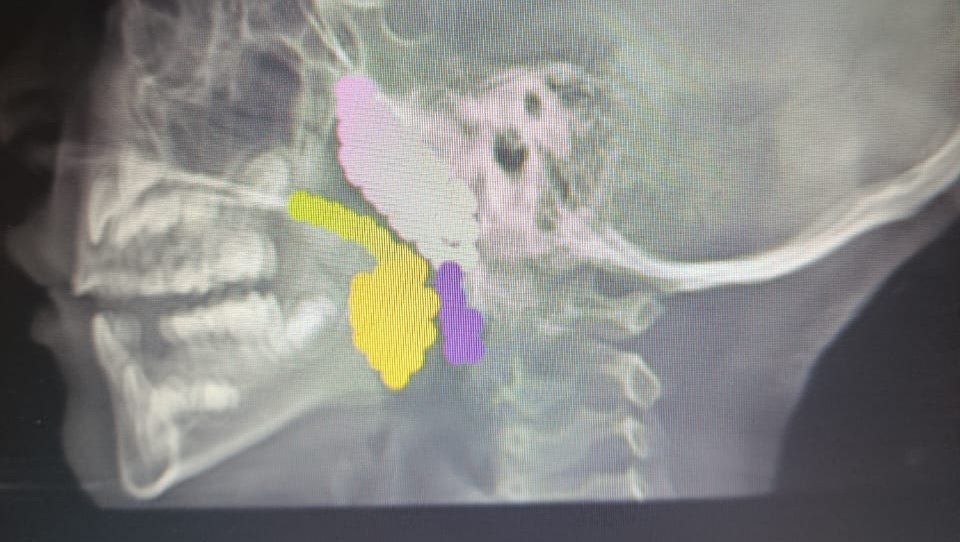

Hello, my name is Fiorella. I'm from Venezuela and I'm 6 years old. I need urgent surgery because I have adenoids, inflamed tonsils, and a deviated septum in my nose. This makes it very difficult for me to breathe every night. My parents don't have the money for this surgery, so any help you can offer is important to me.